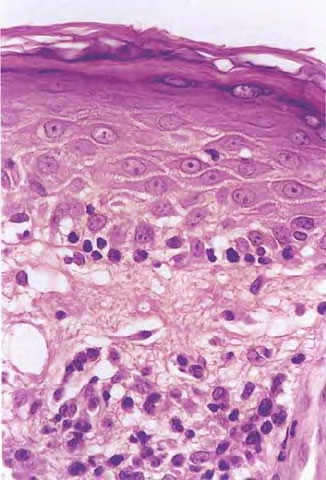

Mycosis Fongoïde =التفطر الكمئي